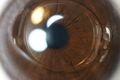

الغرفة الأمامية ( AC ) هي المساحة المليئة بالخلط المائي داخل العين بين القزحية والسطح الداخلي للقرنية ، البطانة .[1] التحدمية والتهاب القزحية الأمامي والزرق هي ثلاثة أمراض رئيسية في هذا المجال. في التحدمية ، يملأ الدم الحجرة الأمامية نتيجة للنزيف ، وغالبًا ما يحدث بعد إصابة العين الحادة. التهاب العنبية الأمامي هو عملية التهابية تؤثر على القزحية والجسم الهدبي ، مع ظهور علامات التهابية في الحجرة الأمامية. في الزرق ، يمنع انسداد شبكة الصلبة التدفق الطبيعي للخلط المائي ، مما يؤدي إلى زيادة ضغط العين ، وتلف تدريجي في رأس العصب البصري ، وفي النهاية العمى .

يتراوح عمق الحجرة الأمامية للعين بين 1.5 و 4.0 ملم ، بمتوسط 3.0 مم. تميل إلى أن تصبح ضحلة مع تقدم العمر وفي العيون مع فرط طول النظر (بعد النظر) كلما انخفض العمق إلى أقل من 2.5 مم ، يزداد خطر الإصابة بزرق انسداد الزاوية.